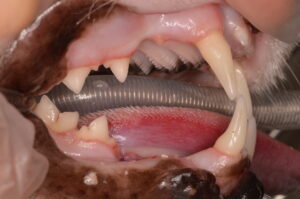

上の写真は今回の猫ちゃんの歯です。歯肉が赤く盛り上がり歯に覆いかぶさっているように見える部分がありますが、これが典型的な吸収病巣の見た目です。歯肉が覆っている部分の下の歯の表面が溶けていることが多いです。

よく「食べたそうにしても食べない」と相談を受けることが多いです。現在のところ、この病気を根治させる治療は確立されておらず、抜歯もしくは溶けている歯冠部(表に見えている部分)を切断することで痛みを取り除く治療が選択されます。今回の猫ちゃんも吸収病巣が痛みの原因と考えられたため、全身麻酔下で詳細な検査と抜歯を行うことになりました。

問題を起こしている歯を抜歯し、他の歯は徹底的に歯周病の原因となる汚れを除去(スケーリング)して終了です。

術後は、よく食べるようになり夜中鳴いていた症状も落ち着いたとのことでした。